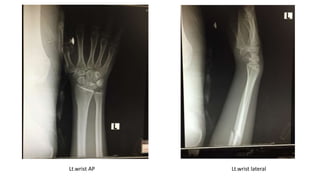

Lt.wrist AP Lt.wrist lateral

Extremities: no wound, deformity at forearm and mild tender Left wrist

and forearm, limited ROM due to pain, radial pulse 2+

Diagnosis: Closed fracture left shaft of ulna